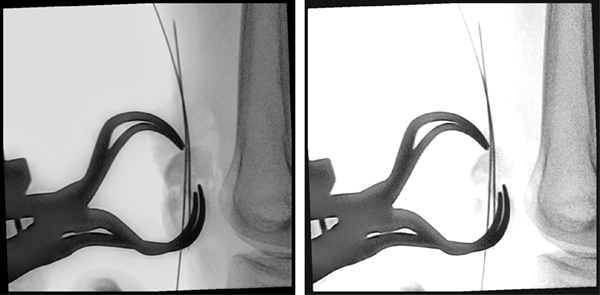

整形外科的処置等で金属インプラントを使用する患者に対して,Philips MetalSmartソフトウェアが自動的に視野内の金属オブジェクトに起因する過度なX線量の増加を防ぐことにより,メタルアーチフェクト(ハレーション)を抑え適切な画質を提供する。

(左)MetalSmartあり(右)MetalSmartなし